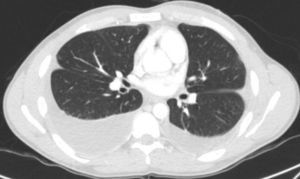

We report the case of a 25-year-old man with bilateral PE (Fig. 1). Complete blood count showed eosinophil concentrations of 3500/mm3, representing 26% of total white blood cells. He had shown similar results on previous tests. PF initially had a turbid appearance, with characteristics of exudate, glucose levels of 64mg/dl and adenosine deaminase levels of 27.7U/l. PF cytology showed no malignant cells and acutely predominant inflammatory cells, with abundant eosinophils (50%–60% of total cell count). PF culture was negative for bacteria, mycobacteria and fungi. Echocardiography showed neither pericardial effusion nor infiltrative cardiomyopathy. Tests were performed to rule out secondary causes of hypereosinophilia, all of which were negative, and after comprehensive hematological studies, the diagnosis was IHES. Response to prednisone 1mg/kg was favorable. The eosinophilia abated initially in peripheral blood and subsequently, after 7 months, in PE. Eosinophil levels in normal PF are low (less than 1%). High levels can be due to multiple causes. The most common causes of EPE are malignant (around 30%–34%1,2), parapneumonic, and tuberculous effusion. Other possible etiologies include asbestos, drug toxicities, parasitical infections, and Churg-Strauss syndrome, or less commonly, viral infections and pulmonary embolism.3 Very little information is available on EPE due to IHES or causes other than those mentioned, as can be surmised from the few cases reported to date.4 The particular interest in this patient is that the disease started only as relapsing EPE. In one of the published cases, the patient had hepatosplenomegaly and ascites combined with bilateral PE, and unlike our patient, the outcome was death. In addition to bilateral EPE, the other patient presented skin lesions which were found to be due to vasculitis.5